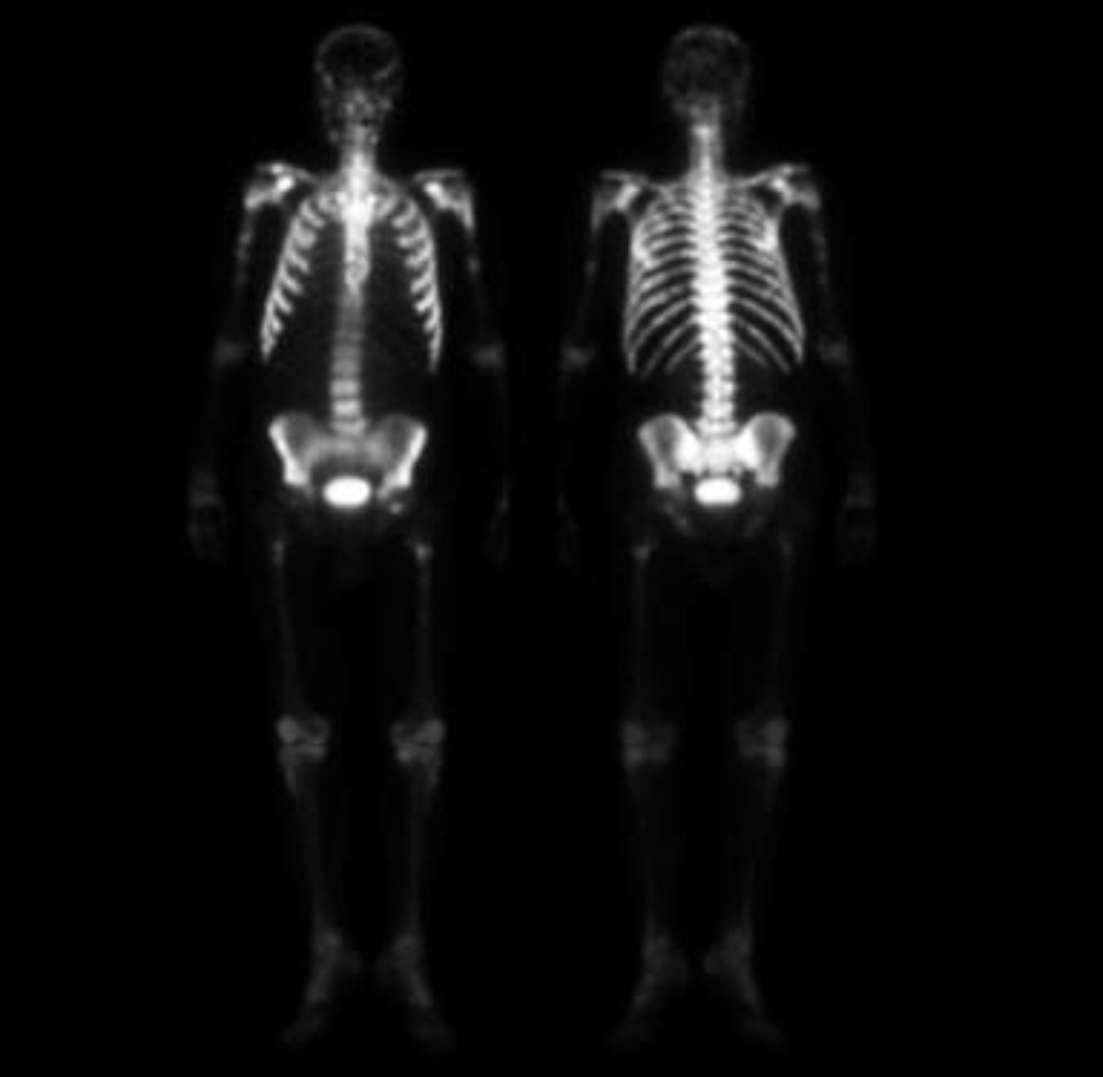

Superscan 2/2 prostate mets

Metabolic superscans usually affect entire skeleton while metastatic are more likely to be axial and proximal appendicular skeleton

breast and prostate most likely to cause superscan